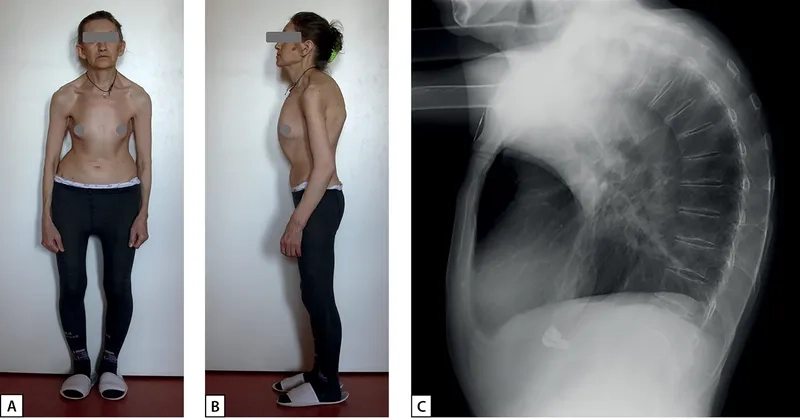

• Key physical Turner syndrome symptoms include short stature (a hallmark Turner syndrome height), a webbed neck, and a low hairline at the back.

Images visual examples of Turner Syndrome